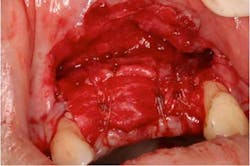

A 43-year-old female with a noncontributory medical history taking no medication and having no known food/drug allergies presented to my general dental office with a chief complaint of having “loose teeth with an underbite.” Clinically, she had generalized, moderate, chronic periodontal disease and was missing teeth Nos. 8 through 10. She had a Class III malocclusion with pathologic flaring of her remaining anterior teeth. She had both vertical and horizontal tissue loss in the No. 8 through 10 region. The patient wore a transitional partial denture to replace the anterior missing teeth that was placed in edge-to-edge occlusion by her previous dentist. (Fig. 1) She did not like having a removable prosthetic and desired a fixed option in the form of implants to replace her missing teeth. I sent her to the periodontist for a periodontal consult for her remaining dentition and dental implants to replace her missing front teeth.

Fig. 2